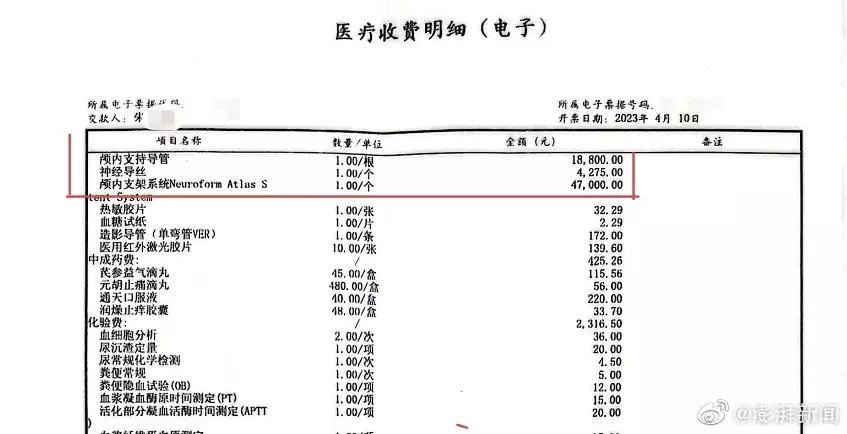

當時醫生告知家屬,如果不予血管內介入治療,患者隨時可能因動脈閉塞導致死亡。經家屬簽字同意,4月6日,齊某再次作為主刀醫生,對朱老翁進行經皮基底動脈支架植入術,術後告知家屬手術成功。手術記錄均顯示,朱老翁安裝了一枚進口Neuroform Atlas 4.5/21支架,病程記錄也多次提到「血管狹窄明顯改善」。朱老翁4月10日「康復」出院,家屬結清了住院醫療費用,合計12萬餘元,部分自費。收據顯示,其中顱內支持導管收費1.88萬,神經導絲4275元,而Neuroform Atlas進口顱內支架為4.7萬元。

醫療費用明細顯示導管、支架等價值7萬元。